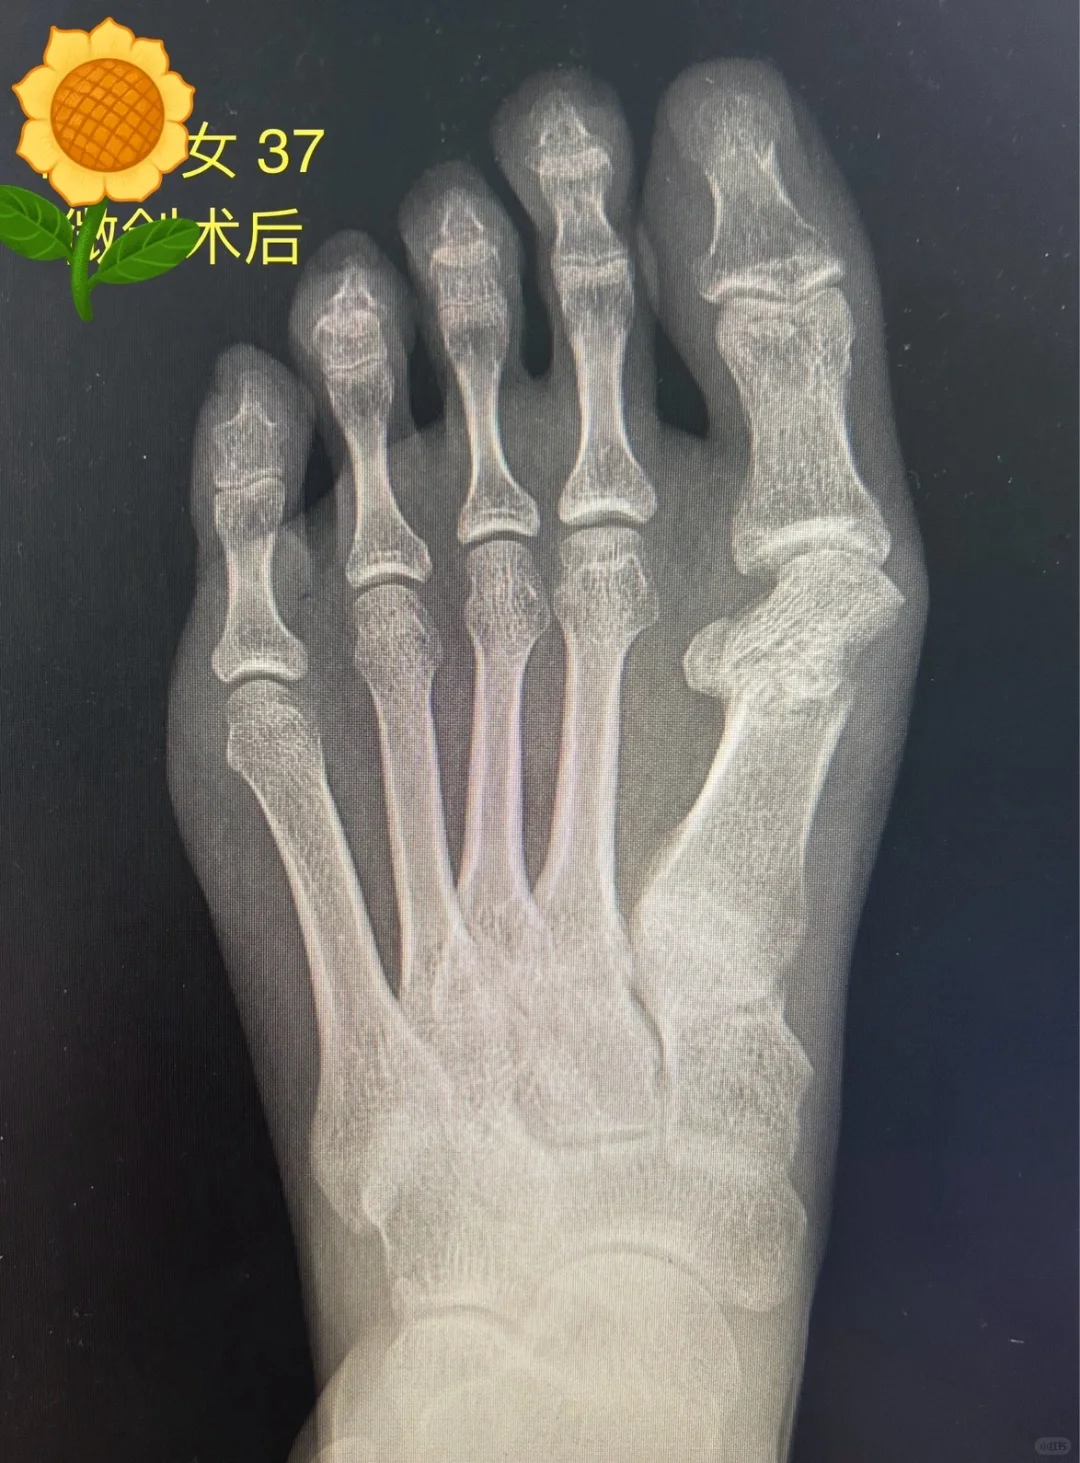

一般都会有拇趾短缩,安全的短缩量在5毫米左右,过度缩短会导致二趾下应力集中,出现转移跖骨痛,也就是横弓重度塌陷。

横弓重度塌陷需要二次手术,或者终身穿着鞋垫,二次手术大致在一年后进行,不要无限期拖延导致跖板断裂。

转移跖骨痛发生率很高,只要拇趾不要短太多,翻修也不难,但跖骨不可再翻修拉长,以免由于张力过大导致疼痛。有三种类型的术后畸形,有不同的翻修方法,不要再做微创翻修了。